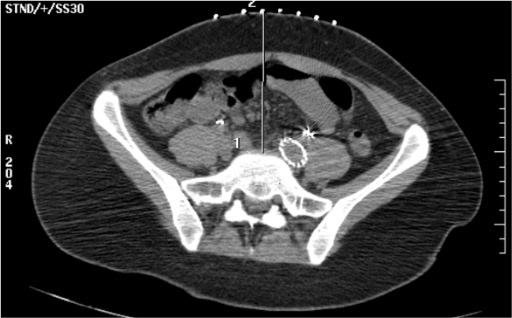

- Primary target: retroperitoneal fat space directly anterior to the L5-S1 intervertebral disc, medial to the common iliac artery bifurcation

- Bilateral needle configuration: two Chiba needles form a "V" with tips converging at the L5-S1 anterior disc/junction

- Correct contrast spread: diffuse retroperitoneal cloud anterior to L5-S1 disc, spreading laterally between the common iliac arteries — no bowel opacification, no intravascular linear flow

- Aortic bifurcation vs. iliac bifurcation: aorta bifurcates at L4; the common iliacs bifurcate into external/internal iliacs at L5-S1 — the SHP lies at this lower (L5-S1) bifurcation

- Depth guide: on axial CT, tips should be in the retroperitoneal fat immediately anterior to the psoas and vertebral body, posterior to the iliac vessels

- Avoid: iliac vein (posterior to artery), ureter (lateral to plexus), bowel loops (replan if any are in path)